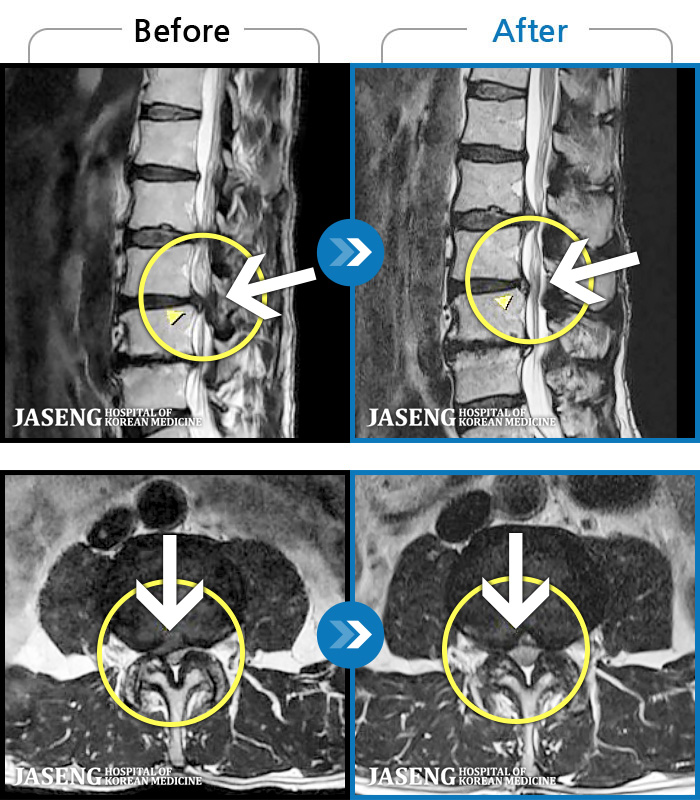

MRI ġ

1,299 MRI ũ ʸ Ȯϼ.